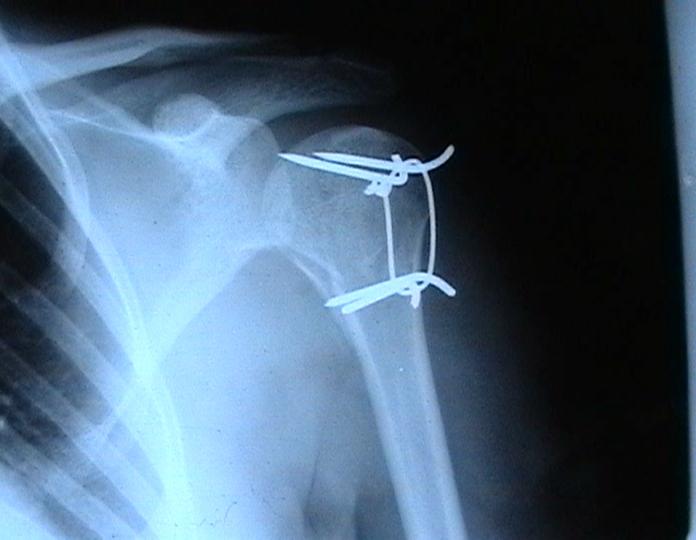

Переломовывих плеча сложная проблема и технически не уверен как для коллег, но для меня сколько я не встречался, технически сложно *вытянуть* вывихнутую головку из-под впадины. Последнее время не применяю пластины для фиксации перелома, а использую спицы и проволочную петлю (тем более часто и густо спонгиозные винты не держатся в головке прочно).

Интересный метод остеосинтеза !

А на сколько он стабилен ?Не происходит ли миграция спиц? Какое количество наблюдений у Вас Евгений? Почему нельзя использовать только проволоку (сформировав для этого туннели в проксимальном и дистальном фрагменте ).

Добавил бы к вашим комментариям ещё - дёшево надежно и мало травматично.

Момент , который следует учитывать при использовании такого рода фиксации - необходимо быть уверенным , что спицы не проникают в сустав, поэтому полезно пользоваться ЭОпом для контроля или интраоперационными рентгенограммами

перед ушиванием раны.

А на сколько он стабилен ?

Фиксация получается достаточно стабильная, правда мои заключения основаны только на клинических наблюдениях, возможности протестировать прочность фиксации в лабораторных условиях нет. Я не автор данного типа фиксации в основе его лежит принцип напряженной фиксации (Weber tension Band fixation). Когда-то у нас использовали фиксатор проф Сеппо при переломах

шейки бедра - принцип работы аналогичен, только менее громоздкие элементы конструкции и более доступные для применения в любых условиях.

Не происходит ли миграция спиц?

Я использую обычные 2 мм спицы и пока в 8 случаях , что применял подобную фиксацию миграции не было, хотя вполне вероятна такая возможность и видимо оптимальнее использовать спицы с резьбой на конце, что должно предотвратить потенциальный риск миграции. Хотя если спица начинает пальпироваться под кожей и доставлять неудобство больному, то её легко удалить в условиях перевязочной. На мой взгляд миграция спицы мложет произойти только тогда,

когда пациент начинает активно работать рукой, к этому времени перелом уже срастется, поэтому опасности скомпрометировать стабильность фиксации уже не будет.

Почему нельзя использовать только проволоку (сформировав для этого туннели в проксимальном и дистальном фрагменте ).

Я такой же практик как и Вы, поэтому решать можно или нельзя использовать только проволочную петлю решать Вам, хотя на мой взгляд, обычная проволочная петля не создает многоплоскостной стабильности фиксации, а только лишь в плоскости проведенных отверстий в проксимальном и дистальном фрагментах и другой момент зачастую такие переломы случаются у пожилых людей с порозной костью, тогда, как понимаете, проволочная петля может легко прорезаться через кость и не о какой стабильной фиксации уже речи быть не может в то время как спицы держаться в порозной кости тем более, что при такой фиксации создается момент силы, направленный не на вытягивание спицы из кости.